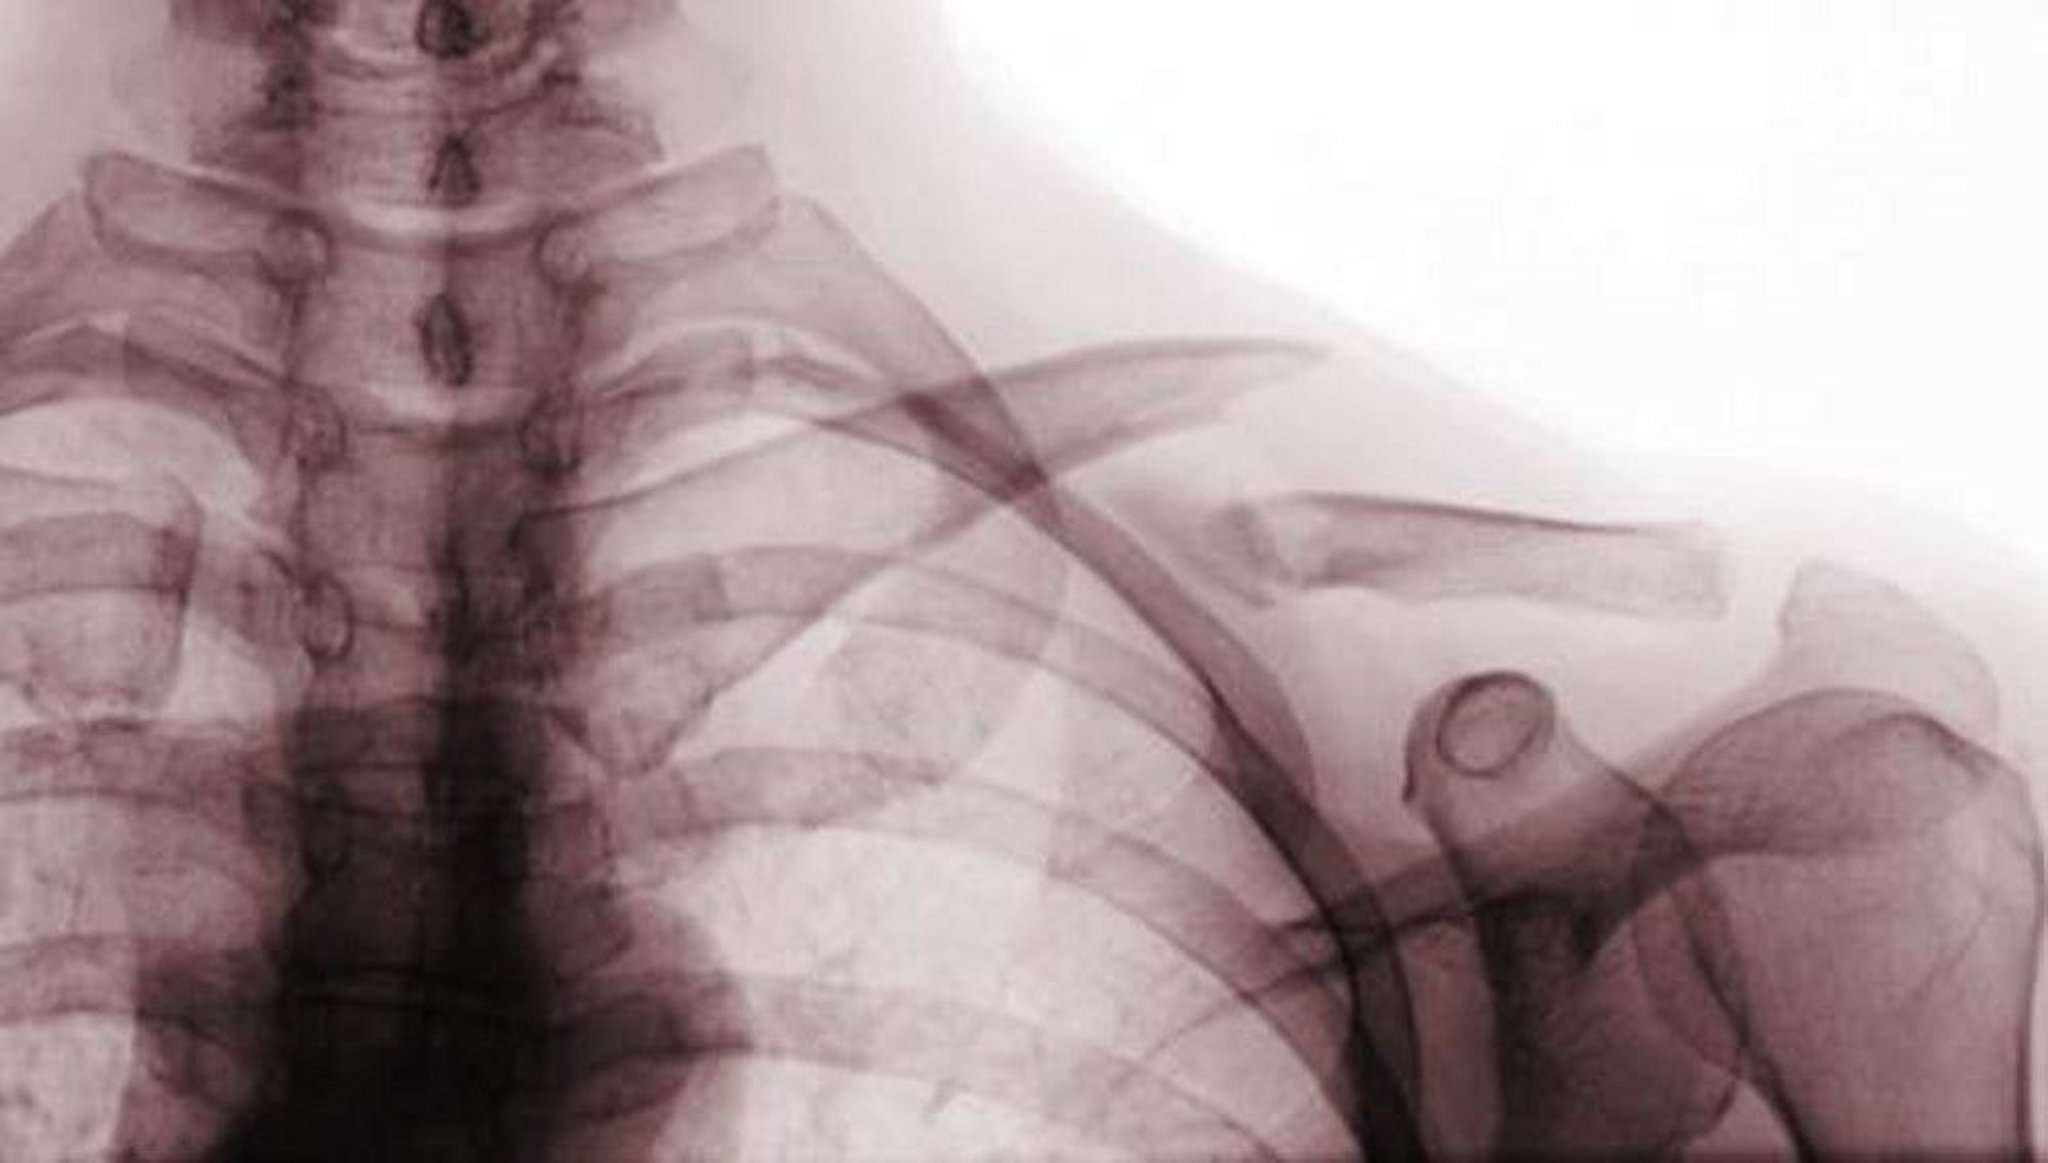

This anteroposterior radiograph view shows a displaced fracture of the middle third of the clavicle (class A fracture).